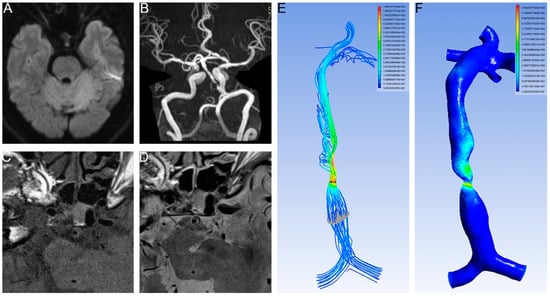

2.3. Calculation of the CFD

| Proximal WSS | 8.68 ± 17.60 | 8.07 ± 4.55 | 0.014 |

| Distal WSS | 48.62 ± 147.26 | 103.78 ± 522.40 | 0.567 |

| WSS ratio | 9.88 ± 21.12 | 16.04 ± 70.63 | 0.557 |

| Proximal velocity | 0.34 ± 019 | 0.38 ± 0.12 | 0.275 |

| Distal velocity | 0.90 ± 1.31 | 1.05 ± 2.04 | 0.858 |

| Velocity ratio | 2.49 ± 2.85 | 2.91 ± 5.54 | 0.811 |

| Proximal WSS | 0.447 | 0.179 | 6.234 | 0.013 | 1.564 | 1.101 | 2.222 |